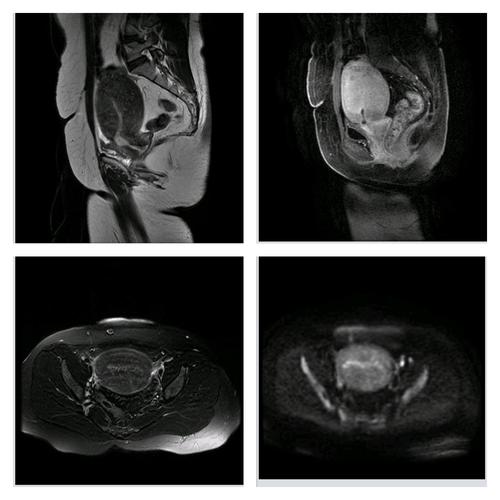

核磁共振平扫加增强,子宫腺肌症

磁共振(mri)女性盆腔,子宫扫描技术

子宫,卵巢mri 正常解剖及生理变化的mri 诊断